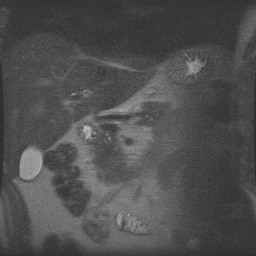

Angio abdominaal